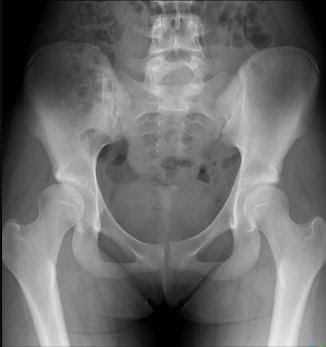

The below X-ray (2) and ultrasound images are from a young teen footballer with an acute, painful ‘pop’ over the high left lateral hip on landing from a jump.

He struggled to bear weight and retired. Examination revealed him unable to single leg squat, Tensor Fascia Lata loading and oblique crunches were sore; exquisitely tender with swelling over 8cm of the iliac crest to the anterior superior iliac spine.

Figure 8 and 9 revealed avulsion of the iliac crest apophysis – rare!!

Figure 8 – AP pelvis xray

Figure 9 – Ultrasound iliac crest